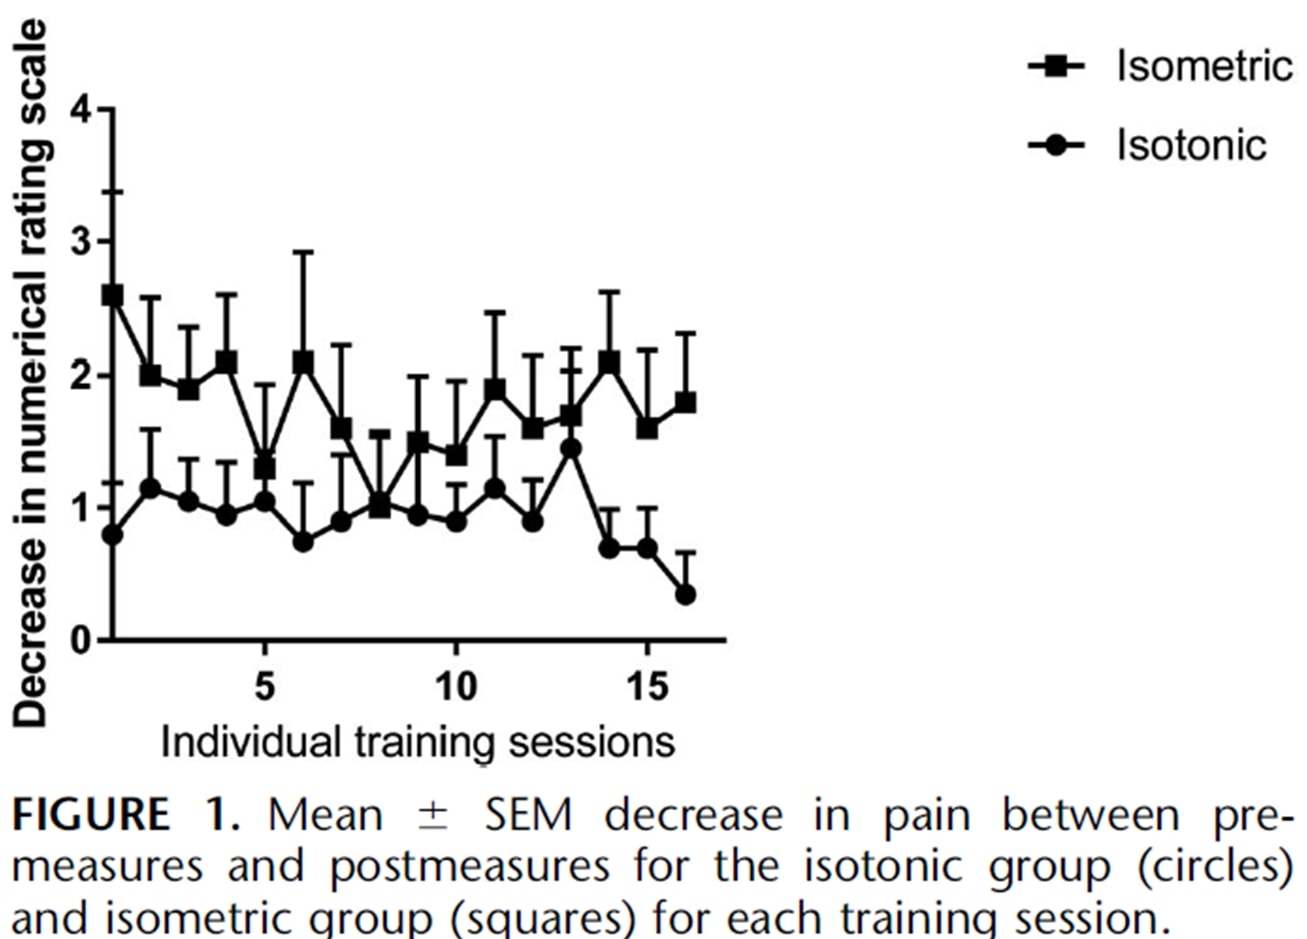

Те же авторы провели повторное исследование в течение сезона с прыжковыми спортсменами два года спустя (Rio et al. 2017), в котором они сравнивали между собой изометрическую программу и изотоническую программу. В этом исследовании результаты были немного более неоднородными в обеих группах с большим немедленным уменьшением боли в изометрической группе: